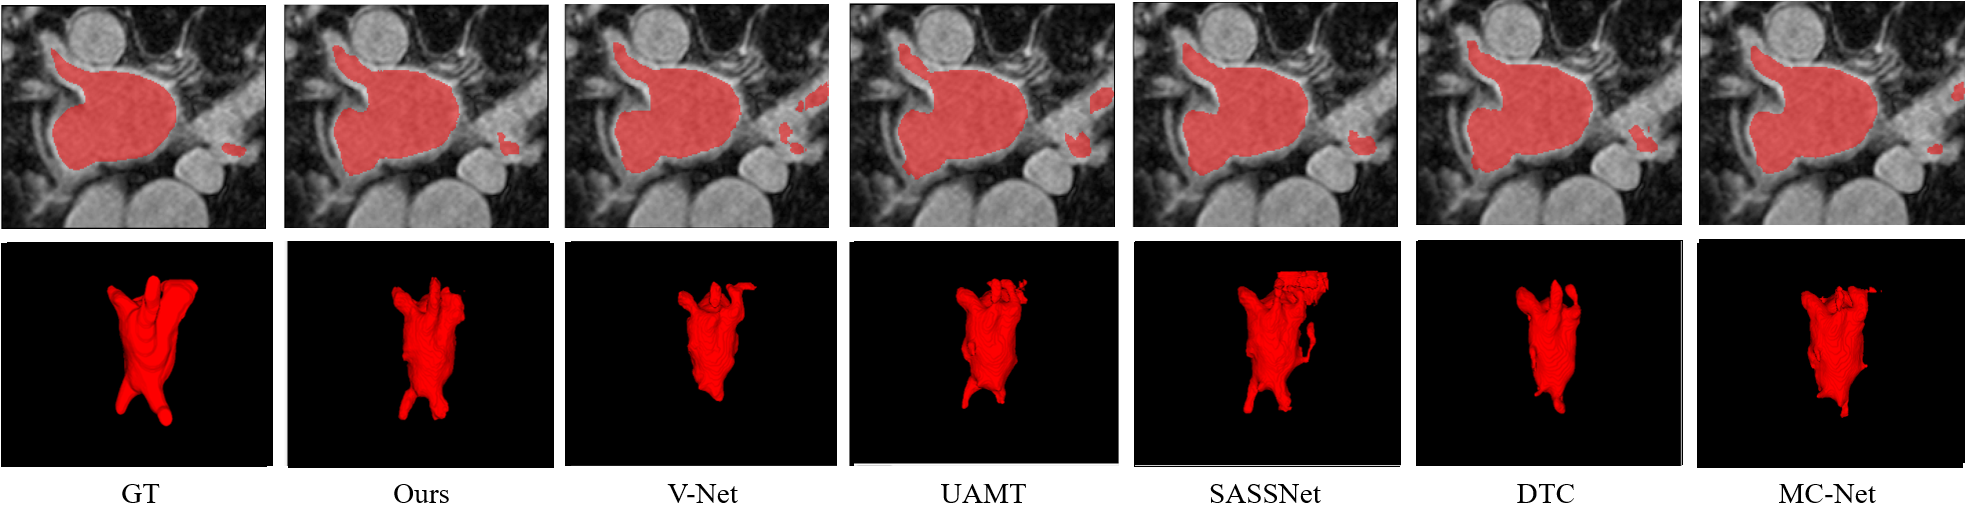

Left Atrial Segmentation Challenge dataset. We evaluated the performance of our proposed network in terms of its accuracy by comparing our results with those of the state-of-the-art models, i.e., domain-agnostic prior [33], UA-MT[10], SASSNet[13], local and global structure-aware entropy regularized mean teacher [34], double-uncertainty weighted method [35], DTC[11], contrastive voxel-wise representation learning [36], and MC-Net[12]. Two semi-supervised settings widely used on the LA dataset were available from a previous study [13] (i.e., using either 10 or 20% of the labeled data). Table I lists the quantitative results of LA segmentation. The results indicate that our proposed method achieves superior results in terms of the DSC, Jaccard index, and HD95 measurements and achieves competitive results on ASSD under the conditions of both 10% and 20% labeled data. Qualitative results are illustrated in Fig. 5. It can be observed that our method has a higher overlap ratio with respect to the ground truth in both 2D and 3D visualizations, thereby producing fewer false positives.

Recent semi-supervised segmentation approaches in medical imaging have demonstrated promising results by employing various techniques, such as consistency regularization [10, 11], pseudo-labeling [12], and adversarial learning [13]. However, previous methods train the network with the outputs obtained from the final layer, which complicates learning of global features by the network. The proposed method is effective for learning both local and global contexts by embedding voxel-level features with voxel-level feature layers and voxel-level feature discriminators (Table I and Fig. 5). We achieved a more structured representation space (Fig. 7 b) by defining voxel-level feature (including global and local context) relations in the representation space. On comparison with a previous method [13] which also included global contextual information with the discriminator and SDM, our method achieved superior results (Table II), particularly for multiclass datasets. By learning class-specific voxel-level features using BYOL[15] and a multitask discriminator, we achieved a more structured representation space (Fig. 7 and Table III) and precise segmentation results for the multiclass dataset (Table II and Fig. 6). This indicates that our method is effective for learning feature relations across different classes. Moreover, as presented in Table IV, significant performance improvements can be observed for simultaneous use of the voxel-wise feature discriminator and voxel-wise representation learning; this implies that the unlabeled data distribution follows the labeled data distribution as we intended (Table III), thereby embedding rich feature representation. In future studies, we can improve the results by suggesting a more efficient method to enable unlabeled data to follow the distribution of labeled data.